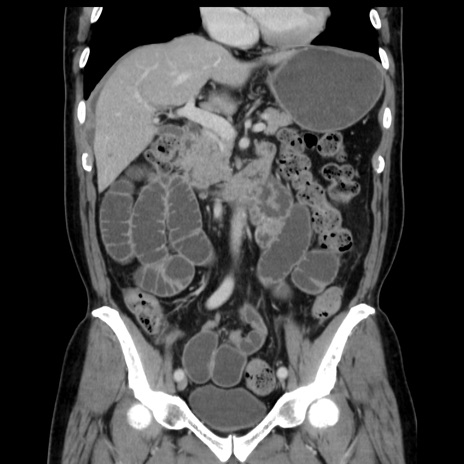

症例16(冠状断像)

【症例】 70歳代男性

【主訴】 腹痛、嘔吐

【現病歴】 約1ヶ月前より間欠的に腹痛と嘔吐あり、当院消化器内科を受診したところCTで多発する肝臓のLDAを指摘され、精査中であった。以降は消化器症状は安定していたが、2日前より嘔気と腹痛があり、同日より排便・排ガスが消失した。改善認めず、 本日、救急外来を受診した。

【既往歴】 大腸ポリープ切除後。

【身体所見】意識清明・会話良好、BT 36.3℃、BP 127/80mmHg、 P 80bpm、腹部:膨満あり、平坦・軟、上腹部正中および下腹部正中に圧痛あり、反跳痛なし、筋性防御なし。

【データ】WBC 7200、CRP 0.77

横断像